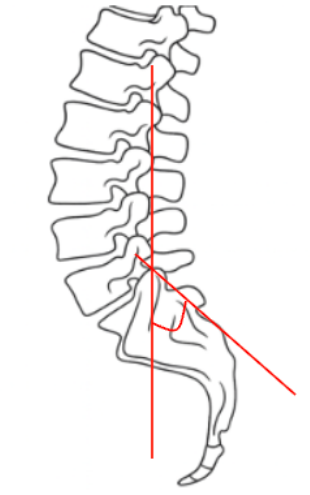

1) Description of Measurement

Boxall’s Angle, also known as the Sacral Inclination Angle, is a radiographic parameter used to assess sacral orientation relative to the vertical axis of the body. It quantifies the anterior tilt of the sacrum, serving as an indirect measure of lumbosacral alignment and pelvic posture.

This measurement is especially useful in evaluating spondylolisthesis, sagittal imbalance, and pelvic compensation. An increased Boxall’s Angle indicates a more anteriorly inclined sacrum and, consequently, greater lumbar lordosis and shear stress across the lumbosacral junction. A reduced angle corresponds to posterior pelvic rotation, often seen in flat-back or compensatory alignment patterns.

2) Instructions to Measure

• Obtain a standing lateral lumbosacral X-ray including the full sacrum and lumbar spine.

• Identify the posterior surface of the sacrum—a straight line can be drawn along its posterior cortical margin.

• Draw a vertical reference line perpendicular to the horizontal (ground) plane.

• Measure the angle formed between the posterior sacral line and the vertical reference line.

• This is the Boxall’s Angle (Sacral Inclination).

• The angle opens anteriorly, representing the degree of sacral tilt relative to the vertical axis.

• Record the result in degrees (°).

• For consistency, ensure that the patient’s posture is neutral (knees extended, pelvis level) during X-ray acquisition.